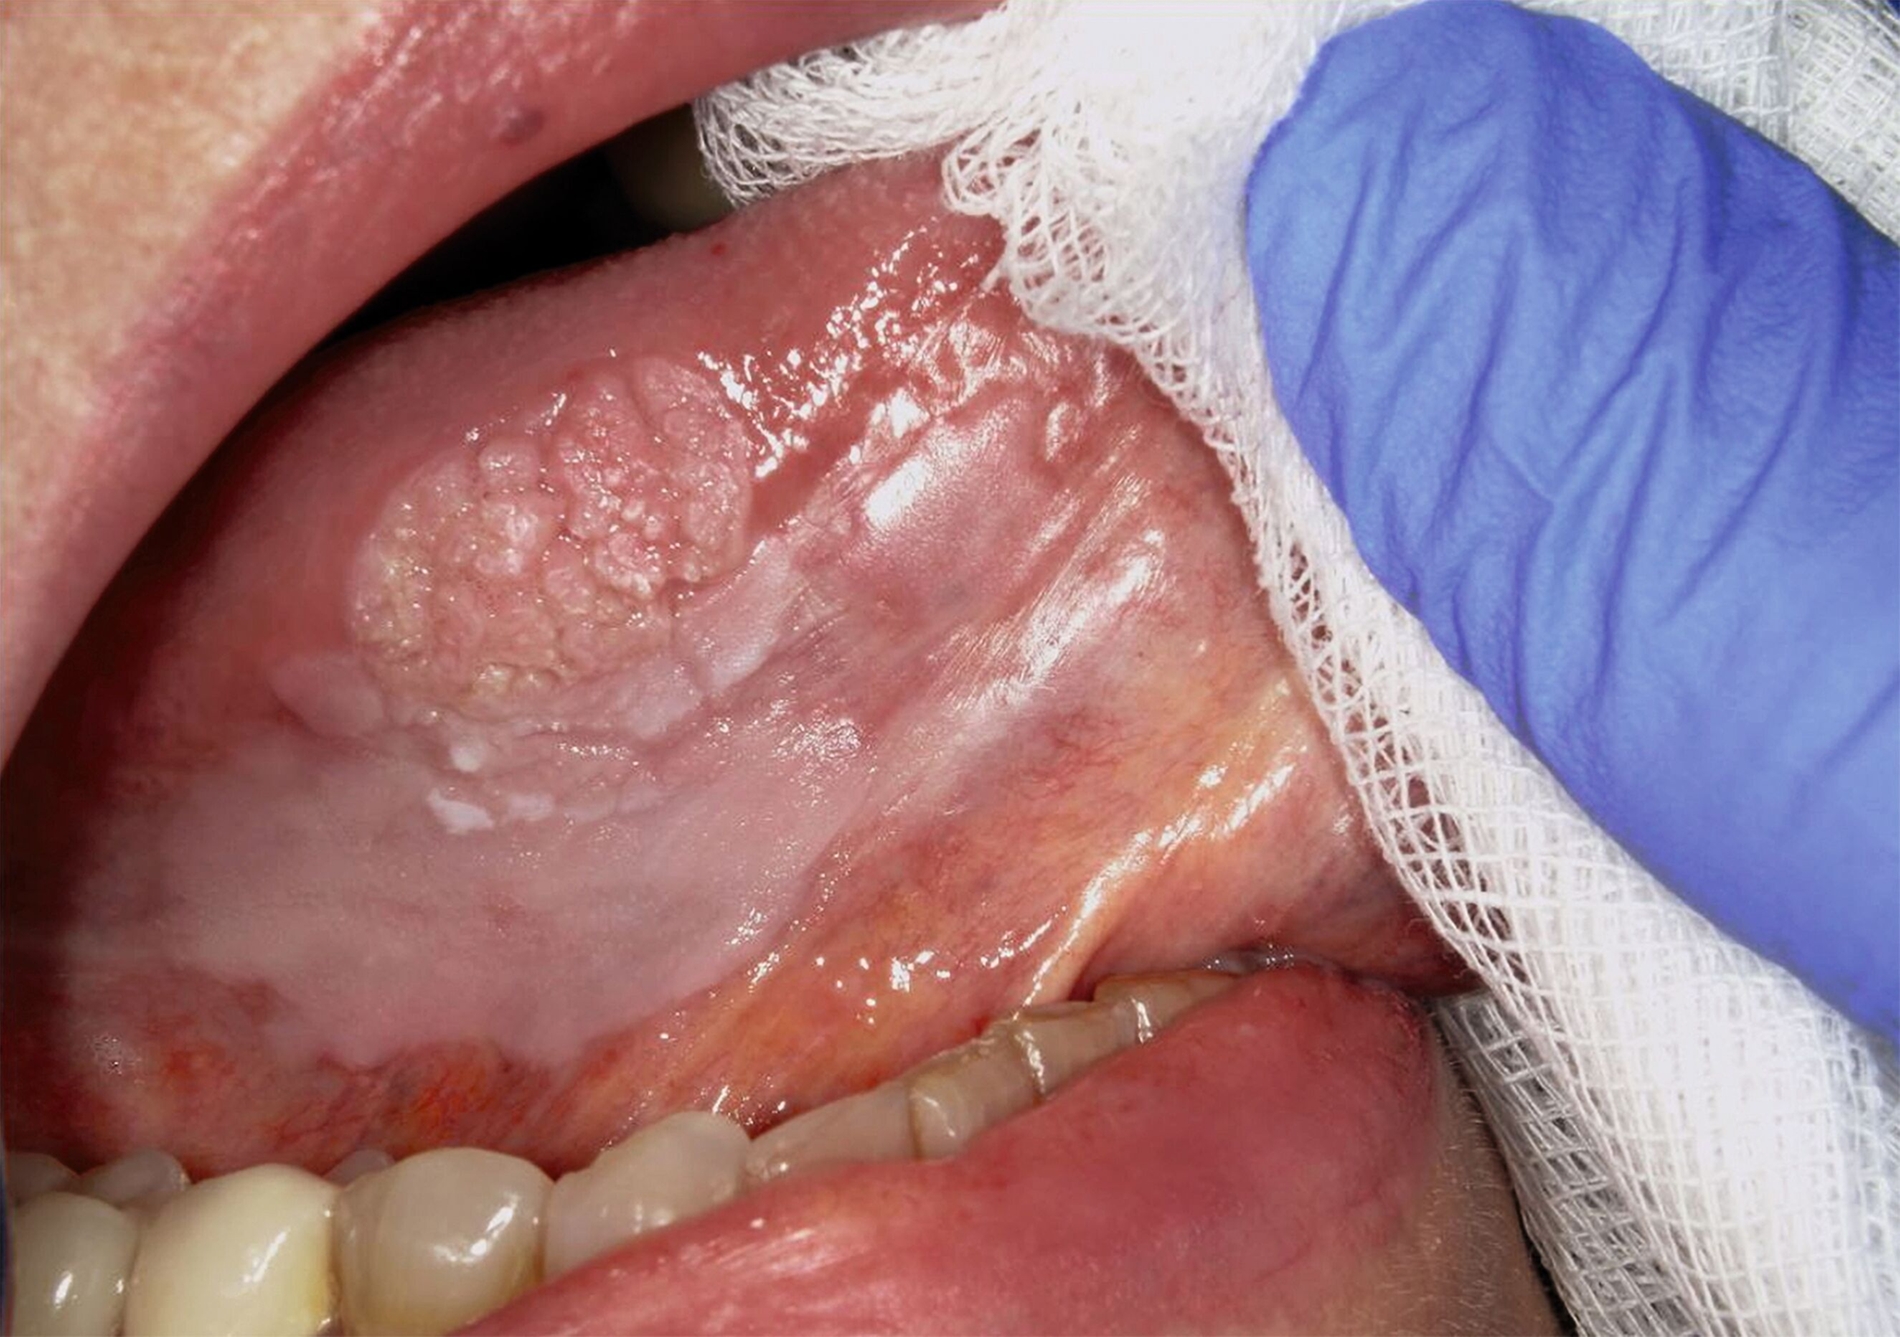

Die Leukoplakie äußert sich in Form von weißlichen Flecken oder Plaques auf der Mundschleimhaut, die nicht abgewischt werden können. Sie sind in der Regel schmerzlos, können aber durch ihre Beschaffenheit – meist rau oder leicht erhaben – auffallen. Am häufigsten sind sie an der Wangeninnenseite, am Alveolarfortsatz, an der Zunge, am Mundboden oder an den Lippen zu finden [Kämmerer et al., 2017; Speight et al., 2018]. Je nach Aussehen und histologischer Beurteilung unterscheidet man die homogene Leukoplakie von der inhomogenen Leukoplakie. Die homogene Leukoplakie zeigt sich als gleichmäßig weißer, glatter oder leicht rauer Fleck (Abbildung 1). Ihr Risiko, bösartig zu entarten, gilt als gering. Inhomogene Leukoplakien haben im Gegensatz dazu ein erhöhtes Entartungsrisiko und lassen sich in weitere Formen unterteilen: die gesprenkelte Form, auch als Erythroplakie bezeichnet (eine Mischung aus weißen und roten Arealen, wobei der weiße Anteil überwiegt), die noduläre Form (kleine, polypenartige Vorwölbungen mit rundlichen, roten oder weißen Erhebungen) und die verruköse Form (gekennzeichnet durch eine gefurchte oder warzenartige Oberfläche) (Abbildungen 2 und 3) [Kämmerer et al., 2017; Warnakulasuriya et al., 2016].

Trotz sorgfältiger Probebiopsie kann es in komplexen Fällen zu einer Diskrepanz zwischen dem histopathologischen Ergebnis und dem klinischen Befund kommen. Die S2k-Leitlinie „Diagnostik und Management von Vorläuferläsionen des oralen Plattenepithelkarzinoms in der Zahn-, Mund- und Kieferheilkunde“ empfiehlt in solchen Fällen eine erneute histologische Überprüfung oder eine Überweisung in eine entsprechende Fachklinik [van der Waal, 2009] Die Abbildungen 7 bis 9 zeigen die Entwicklung einer Leukoplakie der Zunge (Abbildung 7), ihre Transformation in ein orales Plattenepithelkarzinom (Abbildung 8) sowie den klinischen Situs nach chirurgischer Therapie (Abbildung 9).